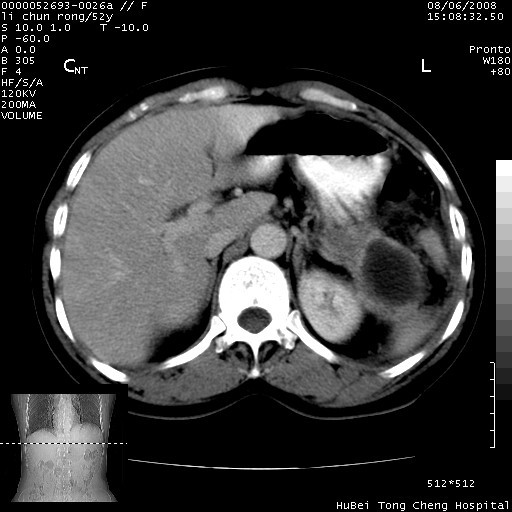

以下是引用云翔在2008-8-7 6:20:00的发言:[br]胰尾部囊性病变,考虑假囊肿,结合实验室检查疾病史

以下是引用zjzjr在2008-8-7 8:38:00的发言:[br]支持胰腺炎伴假囊肿形成,左肾小囊肿.少量腹水.

以下是引用随光逐影在2008-8-7 9:12:00的发言:[br]1)考虑胰腺炎伴假性囊肿形成可能性大;胰腺囊腺瘤待排。2)左肾小囊肿。3)少量腹水。